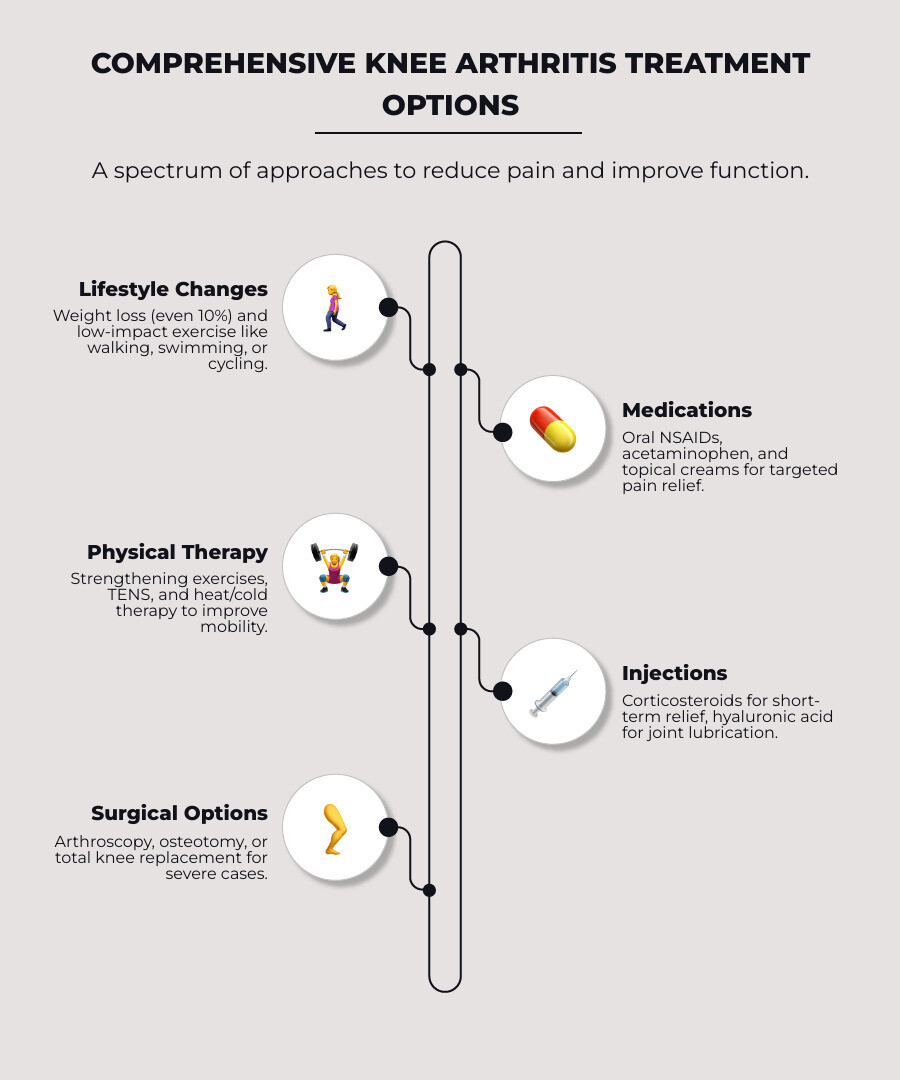

Main Treatment Categories:

- Lifestyle Changes: Weight management and low-impact exercise (walking, swimming).

- Therapies & Medications: Physical therapy, oral NSAIDs, and topical creams.

- Injections: Corticosteroids for short-term relief and hyaluronic acid for lubrication.

- Surgery: Procedures ranging from arthroscopy to total knee replacement for severe cases.